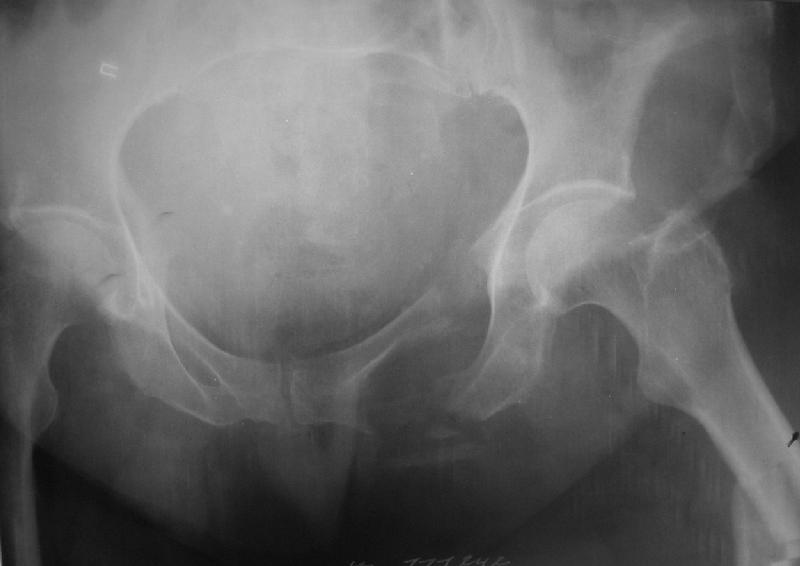

Здравствуйте уважаемые коллеги! Поступила пациентка, 61г, через 1 месяц после травмы, с двусторонним ротационно-нестабильным повреждением тазового кольца: перелом боковых масс крестца с обеих сторон, переломы лонной и седалищной костей слева, отрывные переломы передних остей левой подвздошной кости, сегментарный перелом левой подвздошной кости. Кроме того у пациентки имеется сегментарный перелом левого бедра. Перелом бедра не вызывает вопросов - планируем блокируемый остеосинтез стержнем, а вот при обсуждении тактики лечения переломов костей таза возник вопрос о необходимости синтеза остей подвздошной кости, учитывая сроки с момента травмы и наличие остеопороза могут возникнуть технические сложности. Если у кого-нибудь собственный опыт или ссылки на литературу об отдаленных результатах при не восстановлении сгибательного аппарата бедра?

Уважаемые коллеги, в продолжение обсуждения перелома костей таза с отрывами остей досылаю R-снимки (КТ и КТ с 3d реконструкцией)